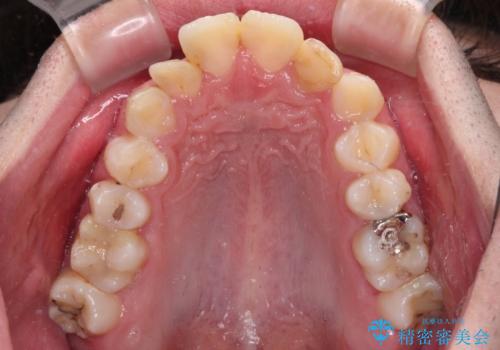

口元はやや突出感があったため、上下左右の第一小臼歯4本を抜歯してワイヤー矯正にて抜歯矯正を行うこととしました。

また、左右ともに最後臼歯が交叉咬合になっており、外側に飛び出している上顎の最後臼歯を補助装置を利用して、積極的に内側に引き込むようにしました。